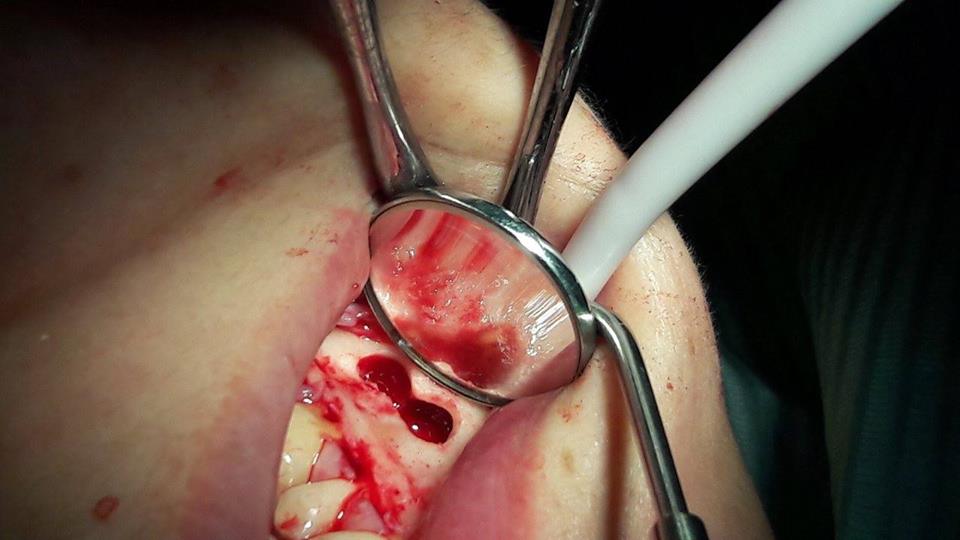

Apicotomy and removal of the cyst of the tooth

Due to unsuccessful endodontic treatment of the first left lower molar, the patient developed a cyst. To preserve the tooth, repeated endodontic treatment was performed, as well as apykotomy (resection of the apex of the tooth root) and the cyst was removed.